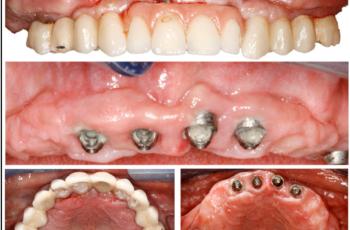

Tratamiento no quirúrgico de la periimplantitis. A propósito de un caso... Cirugía periodontal y periimplantaria | UIC Tratamiento no quirúrgico de la periimplantitis. A propósito de un caso... Se presenta el caso de una paciente de 58 años de edad, sin antecedentes médicos de interés y no fumadora. El motivo... Etiología, diagnóstico y tratamiento de la periimplantitis: Caso... Tto. Periimplantario | UV Etiología, diagnóstico y tratamiento de la periimplantitis: Caso... Presentamos nuevo caso clínico realizado por los doctores Manuel Rodríguez Aranda, Francisco... Efectividad del Tratamiento en Periodontitis Agresiva Tto. Periodontal | UIC Efectividad del Tratamiento en Periodontitis Agresiva El mantenimiento de la dentición natural en estado de salud ha sido un objetivo importante en... Injerto gingival libre alrededor de implantes dentales. A propósito de un... Cirugía periodontal y periimplantaria | UIC Injerto gingival libre alrededor de implantes dentales. A propósito de un... La cirugía mucogingival reconstructiva alrededor de implantes corrige los defectos de la... Terapia mucogingival en implantes: corrección de las secuelas mucosas de... Cirugía periodontal y periimplantaria | UV Terapia mucogingival en implantes: corrección de las secuelas mucosas de... El caso que se presenta a continuación muestra una resolución impecable de un defecto mucogingival... Importancia del mantenimiento en la evolución de un paciente con... Mantenimiento | UV Importancia del mantenimiento en la evolución de un paciente con... La periodontitis agresiva se define como una enfermedad de rápida progresión en la destrucción... Tratamiento de Recesiones Gingivales Clase III de Miller mediante técnica... Cirugía periodontal y periimplantaria | UIC Tratamiento de Recesiones Gingivales Clase III de Miller mediante técnica... El caso clínico que presentamos a continuación es el de una paciente que acude a la consulta... Tratamiento de un paciente con periodontitis crónica moderada generalizada Tto. Periodontal | UIC Tratamiento de un paciente con periodontitis crónica moderada generalizada El caso clínico que se presenta a continuación, muestra el tratamiento de una paciente...